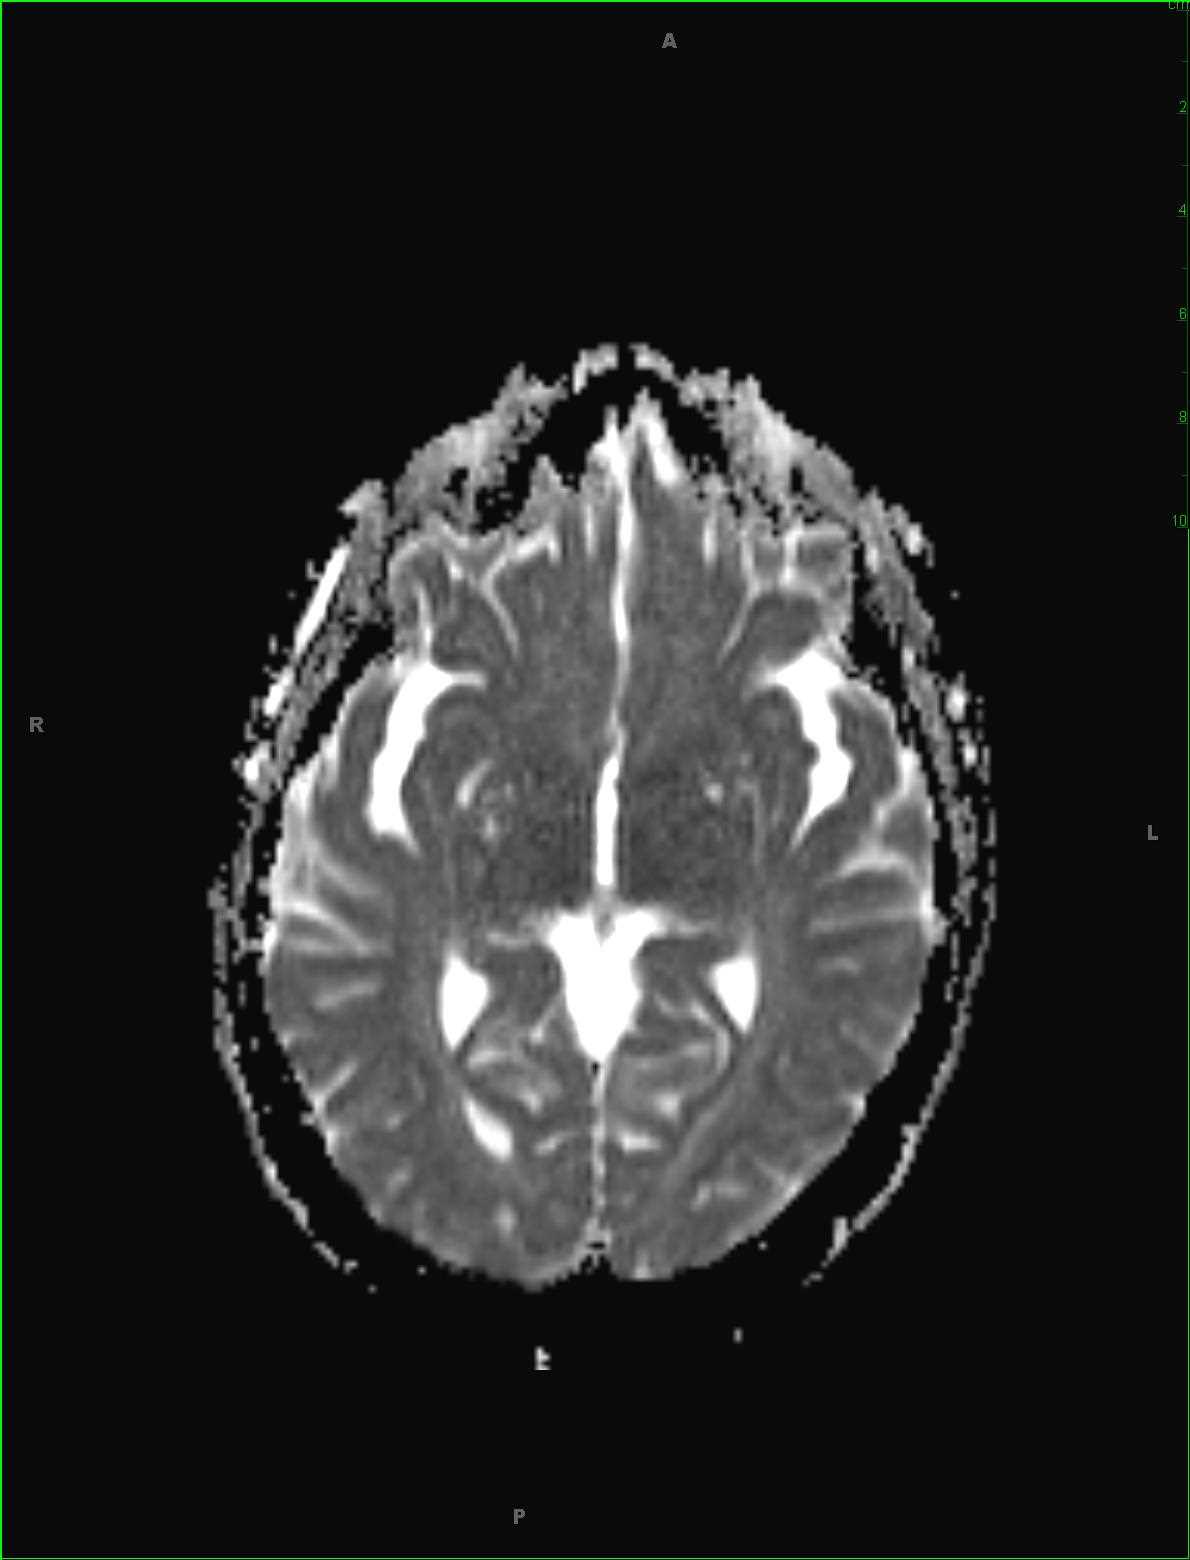

48-year-old female who attempted suicide by overdosing on acetaminophen. There is hyperintense FLAIR signal abnormality within the dorsomedial aspect of the thalami and extending into the midbrain. There is abnormal diffusion restriction at the sites without contrast enhancement. Given the stated clinical history, the findings are most compatible with acute hepatic encephalopathy in the setting of acetaminophen toxicity. Hepatic encephalopathy may be either acute or chronic. Acute cases typically arise in the setting of acute hepatic failure, such as in this case. Chronic cases tend to occur in patients who undergone prior portosystemic bypass without associated intrinsic hepatocellular disease or in patients with hepatocellular dysfunction and portosystemic shunting. Classic MR imaging abnormalities include high T1 signal intensity within the globus pallidus with mild cases demonstrating T2 FLAIR symmetrically hyperintense signal in the insula, thalami, and posterior limbs of the internal capsules. Diffusion signal abnormality may be present and can reverse if therapy for the underlying acute decompensation is instituted early. The extent and severity of the FLAIR and diffusion-weighted imaging correlates with the plasma ammonia level.